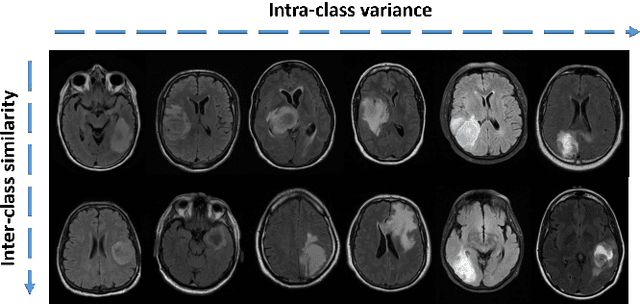

Abstract:While deep learning approaches have shown remarkable performance in many imaging tasks, most of these methods rely on availability of large quantities of data. Medical image data, however, is scarce and fragmented. Generative Adversarial Networks (GANs) have recently been very effective in handling such datasets by generating more data. If the datasets are very small, however, GANs cannot learn the data distribution properly, resulting in less diverse or low-quality results. One such limited dataset is that for the concurrent gain of 19 and 20 chromosomes (19/20 co-gain), a mutation with positive prognostic value in Glioblastomas (GBM). In this paper, we detect imaging biomarkers for the mutation to streamline the extensive and invasive prognosis pipeline. Since this mutation is relatively rare, i.e. small dataset, we propose a novel generative framework - the Sequential Attribute GEnerator (SAGE), that generates detailed tumor imaging features while learning from a limited dataset. Experiments show that not only does SAGE generate high quality tumors when compared to standard Deep Convolutional GAN (DC-GAN) and Wasserstein GAN with Gradient Penalty (WGAN-GP), it also captures the imaging biomarkers accurately.